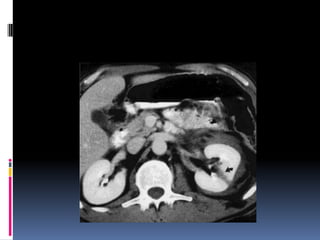

¿LÍQUIDO LIBRE HIPERDENSO? Diagnóstico: RUPTURA VESICAL